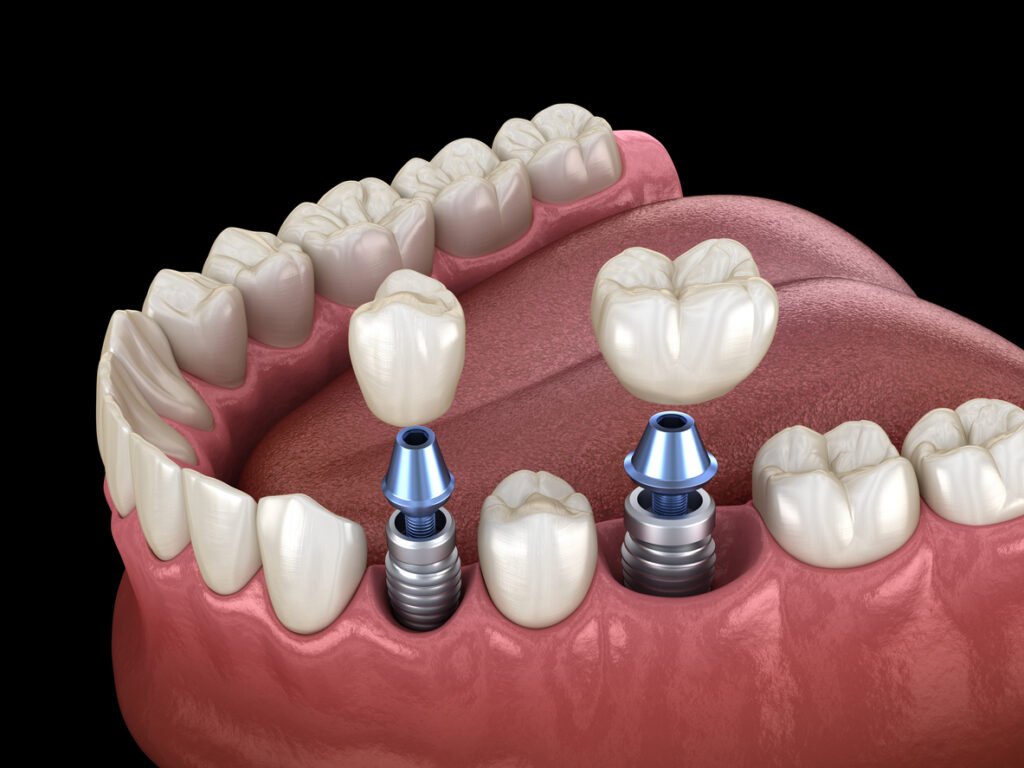

Dental implants provide a permanent, natural-looking solution for missing teeth, restoring both function and appearance. At Siddiqui Dental Clinic, we utilize advanced technology to ensure precise and comfortable implant placement. Our expert team carefully assesses each patient to create a personalized treatment plan for optimal results. Implants help restore chewing ability, improve speech, and maintain overall facial structure and jawbone health. They are crafted from durable, high-quality materials, ensuring long-lasting strength and stability. The procedure is minimally invasive, prioritizing patient comfort at every stage. Dental implants integrate seamlessly with surrounding teeth, providing a natural, confident smile. Proper care and maintenance allow implants to last a lifetime while maintaining functionality. Patients regain confidence in their appearance and enjoy improved oral health. Our team guides patients through every step, offering professional support and advice. We focus on delivering results that balance aesthetics with practicality. Experience renewed confidence and a beautiful, fully functional smile with expertly placed dental implants at our clinic.